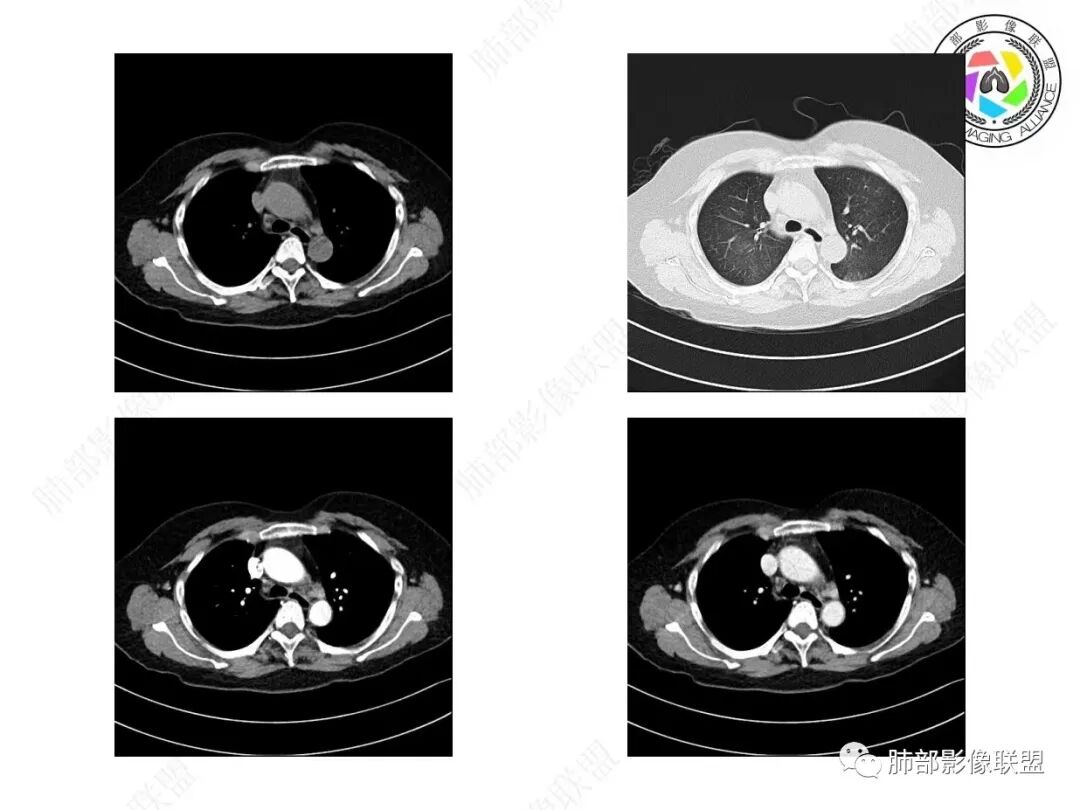

秦化君:老年女性,一月病史。双肺广泛不均匀分布磨玻璃影,边缘部分模糊,左下肺实变,密度不均。考虑:1.感染性病变PCP。2.非感染血管炎。

王江涛:考虑左肺下叶粘液腺癌,双肺播散。

金豆:两肺多发,左肺下叶实变+磨玻璃,有结节感,结核可能,鉴别粘液腺癌。

放射小白:中年女性,间断咳嗽一月余,咳痰4天;影像表现:右肺中下叶、左肺下叶见磨玻璃密度影,左肺下叶局部可见实性密度影,实性成分内部可见变窄、截断支气管通气征,增强实性成分内部可见血管造影征,但是血管扭曲,结合以上分析两肺符合肺黏液腺癌,不排除肺腺癌。

谢加平:中年女性,慢性干咳史,少量白色粘液痰,左肺下混合密度影,实性密度比胸壁软组织低,周围见大片磨玻璃密度,边缘模糊,叠瓦征分布,实边区内血管束边缘模糊(需重建血管束确认分支有无消失),余肺叶散在分布磨玻璃病灶(气道种植),抗炎治疗无效,左肺下叶符合肺炎型粘液腺Ca并双肺叶气道飘散转移!

患者,女性,57岁。咳嗽1月、咳痰4天,亚急性病史,抗炎效果不佳,体温不高,痰为白色黏痰,白细胞稍高,主病灶在左下叶,实变+GGO,其余肺也有GGO,伴随有结节。

本例病例老年女性,慢性病程,抗炎效果不佳。CT示左肺下叶实变影,周围可见大片磨玻璃密度影,密度不均。右肺亦见少量斑片状磨玻璃密度影。增强可见血管造影征,结合南大分析,排除真菌,结核等,答案就呼之欲出了。